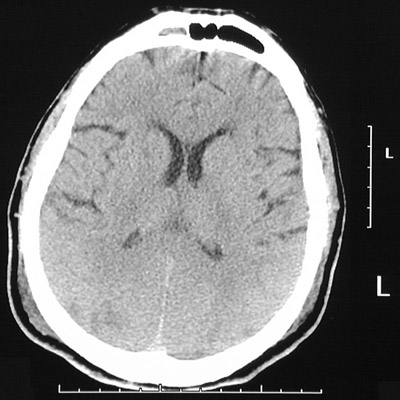

This head CT scan reveals occipital lobe acute infarctions characterized by loss of gyral distinction along with darker white matter, compared to the uninfarcted frontal lobes.